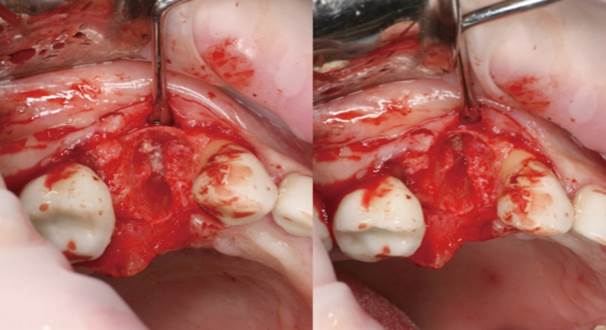

Clinical case: Extraction, immediate implant placement, & provisionalization

- Courtesy of Dr. Iulian Filipov, Romania -

Keywords

AnyRidge, R2GATE, guided surgery, immediate placement, immediate provisionalization, initial stability, Dr. Iulian Filipov, #25, maxillary posterior, immediate loading, Mega ISQ